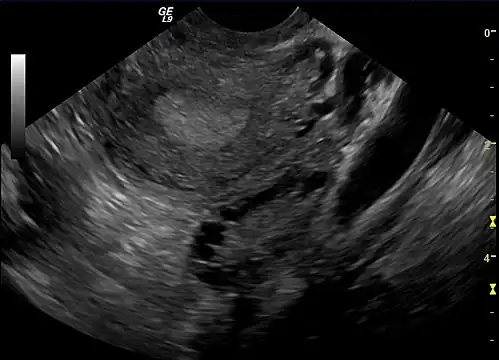

Gynecologic ultrasonography first looks for small ovarian follicles.[75] To count as polycystic ovaries, at least 20 follicles need to be present, smaller than 9 mm. This used to be 12 in older diagnostic criteria.[16] A less clear marker of PCOS is enlarged ovaries.[75] Ovary need to be at least 10 cm3 to count.[16] For sexually active individuals or those that agree, a transvaginal ultrasound approach is preferred. Alternatively, AMH levels can be tested in the blood.[75] Laparoscopic examination may reveal a thickened, smooth, pearl-white outer surface of the ovary. This would usually be an incidental finding if laparoscopy were performed for some other reason, as it would not be routine to examine the ovaries in this way to confirm a diagnosis of PCOS.[78]

-

Transvaginal ultrasound scan of polycystic ovary

Transvaginal ultrasound scan of polycystic ovary -

Polycystic ovary as seen on sonography

Polycystic ovary as seen on sonography